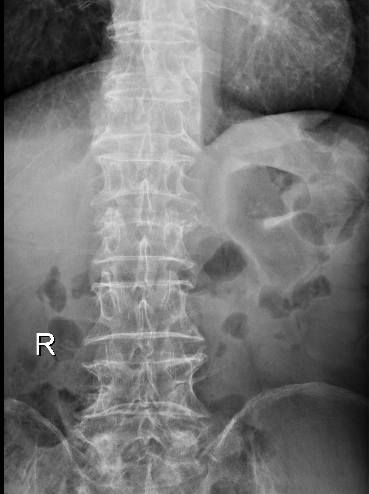

十余年来,我科室相继开展骨质疏松症的相关诊治工作,逐渐形成了自身的诊治体系,后经过整合联系,形成了以骨科二病区为龙头,联合检验科、放射科、内分泌科、血液风湿科等多学科结合、内外协作的骨松诊治MDT模式。目前采用的诊断方式有血钙及维生素ADKE检测、双能X线骨密度检测等,治疗方面也内外兼修,既可应用促成骨的四烯甲萘醌等,抑制骨吸收的唑来膦酸等药物治疗,又可采取椎体强化术、经皮穿刺椎弓根钉置入术等有效手术治疗,可结合患者自身情况,采取合适的治疗手段。开展骨质疏松诊治工作的十几年来,遵循指南,结合当地实际,总结归纳出了一套立足自身实际的诊疗体系,采取药物治疗与手术治疗相结合、因人而宜、综合施治的个体化的综合诊疗方案等。近年来,随着微创理念的推行和ERAS理念的实践,骨科二病区率先在本地区开创性的应用微创经椎间孔入路椎体强化术、经皮穿刺椎弓根钉置入术等先进治疗手段,实现立竿见影的治疗效果,深得广大患者的好评,取得了良好的社会效益和学术影响力,使桓台百姓足不出县即可享受到国内外先进的脊柱外科诊治体验。

术后术前